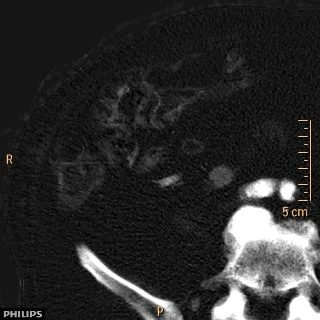

Virtual non-contrast: Comparison to conventional CT shows obvious enhancement visually. On measurement, HU increase from 36 to 82.